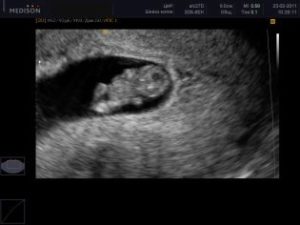

Як виглядає на УЗД

Нижче представляємо вашій увазі знімок УЗ-діагностики, на якому є гематома на матці.